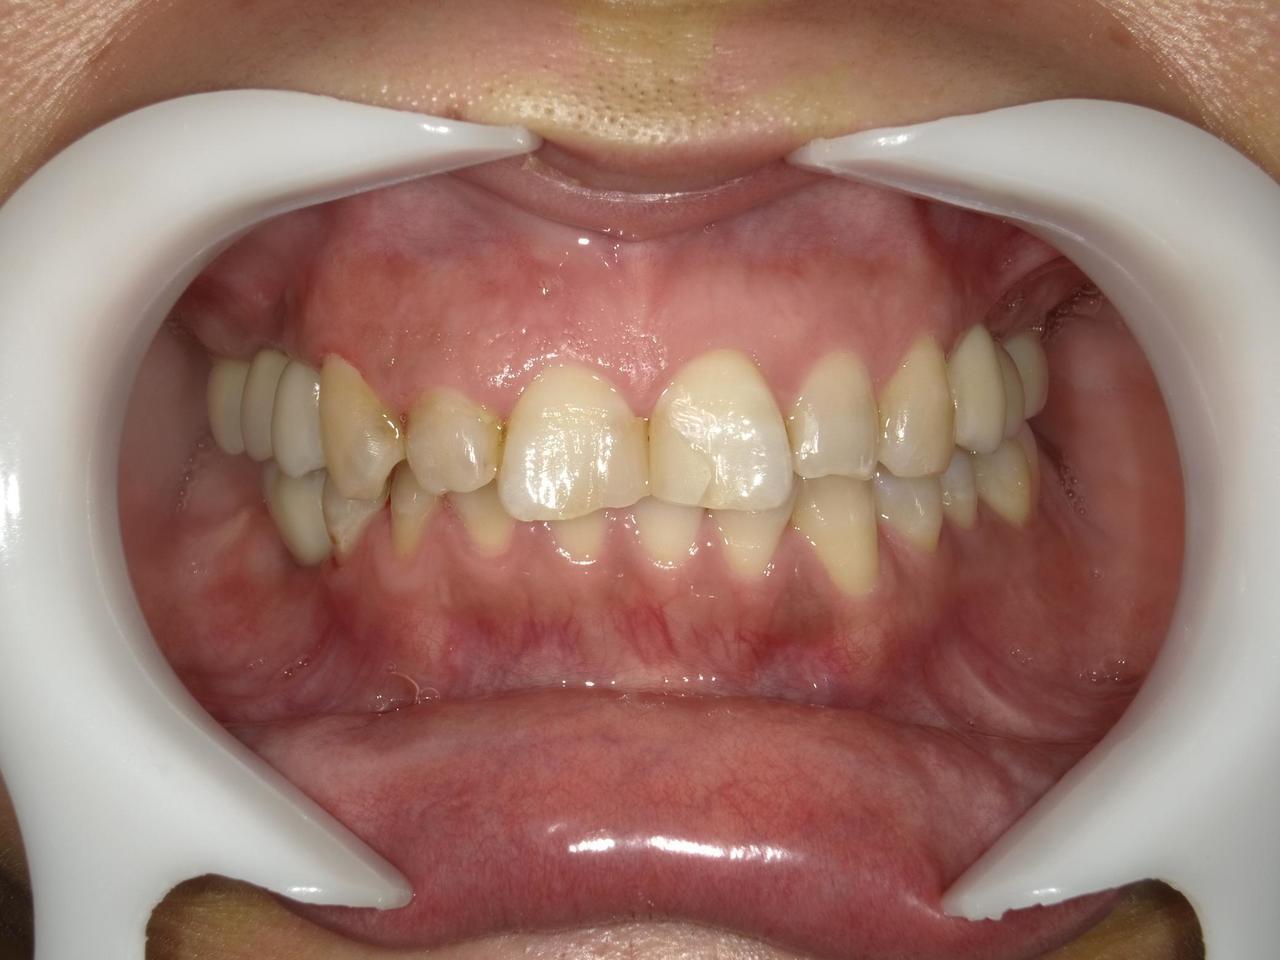

1.左上3番 インプラント抜歯即時埋入即時荷重(手術当日に抜歯を行い、当日に仮歯を入れています。)、左上4番 3ユニット式ブリッジが入るまでの暫間インプラントを埋入して当日に仮歯の装着。 左上5 既存骨3mmのグラフトレスサイナスリフト。最終補綴は、3ユニットジルコニアブリッジで治療を終えた症例

Before

枚方市のインプラントの症例

After

E・S様 女性 60代

患者様の症状としては、左上5番の排膿と重度の歯の動揺、重度の骨吸収、左上3番、中程度の骨吸収と中程度の歯の動揺、自発痛がありました。

治療法としては、左上3456にブリッジ治療が行われていたが、左上5の骨吸収と排膿を認めるために抜歯を行った2か月後に、患者様は、インプラント治療を希望。左上3の骨吸収と動揺も認めていたために、左上3を保存しても将来的な抜歯が予想されたため、左上3抜歯しての左上345の3ユニット式ブリッジ治療の計画を立てインプラント手術を行っています。患者様は、前歯がないことを気にされていたため、左上3番の抜歯と同時の仮歯製作と左上4番暫間インプラントにての仮歯製作を手術と同時に行っています。また、左上3番の歯肉退縮を予防するために、ご自分の歯の一部を温存するルートメンブレンテクニックを行っています。左上5に関しては、既存骨が3mm程度しかないので、グラフトレスサイナスリフトを施行して、表面の骨吸収した部分に骨補填材填入して、ボリュームを維持させていただいています。最終的な3ユニットブリッジは、ジルコニアで製作しています。補綴物の製作に関しては、オールデジタルで行っています。

治療結果は、患者様の希望通り、見えるところの歯がない状態なく、治療を終えることができたことと、また、グラフトレスサイナスリフトを施行することにより、従来のサイナスリフトを施行した場合と比較して、6時か月以上早く治療を終えることができたことと、ルートメンブレンテクニックを行うことで、歯肉退縮を少なくでき、自然な見た目で、最終補綴物を装着できました。従来のGBRやサイナスリフトを行わなかったことにより、短時間で、低侵襲に治療を終えることができ、審美面と機能面の回復を行うことができました。

治療の期間・回数:4か月、10回

治療の価格:814,000円(税込)

治療費の内訳:インプラント基本料(フィックスチャー及び手術費用、投薬費用、レントゲン費用、インプラント上部費用(アバットメントおよびジルコニアクラウンの費用用)右上3番5番 330000円×2 660000円(税込み)オプション費用 右上5グラフトレスサイナスリフト費用 33000円(税込み) 右上3抜歯即時荷重費用 33000円(税込み) 暫間インプラント費用 0円

治療のリスクや副作用:手術後に、痛みや腫れ、出血、合併症などを引き起こす可能性があります。噛む感覚がご自身の歯と異なる場合があります。見た目がご自身の歯と異なる場合があります。手術後にメインテナンスを継続しないと、インプラントが抜け落ちる可能性があります。